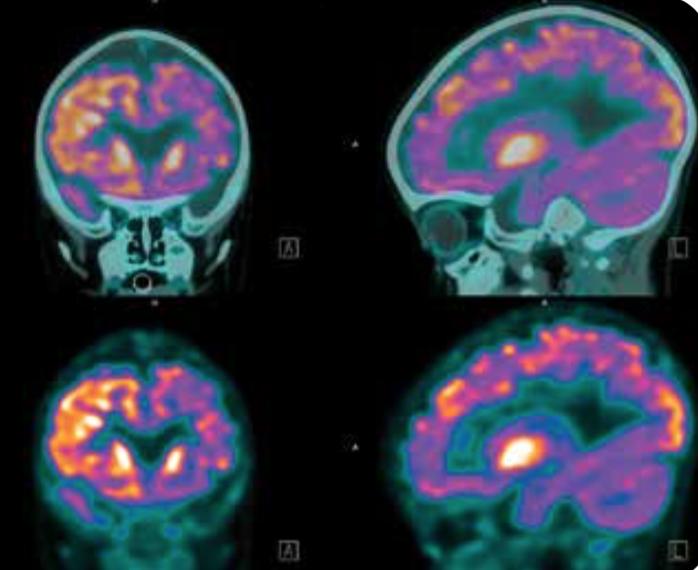

image: Atrial fibrillation patients who use the drug, warfarin, to prevent harmful blood clots from forming in their hearts to lower risk of stroke are at higher risk of developing dementia than patients who use warfarin for non-atrial fibrillation conditions, according to a new study from the Intermountain Medical Center Heart Institute. view more

Credit: Intermountain Medical Center